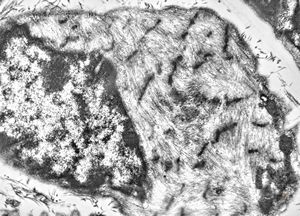

M,56y. | amyloidosis - tendon